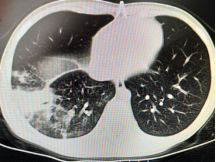

以下为呼吸专业典型病例分享:

图片5:气管内膜结核及重症支原体肺炎所致气道阻塞、塑性支气管束